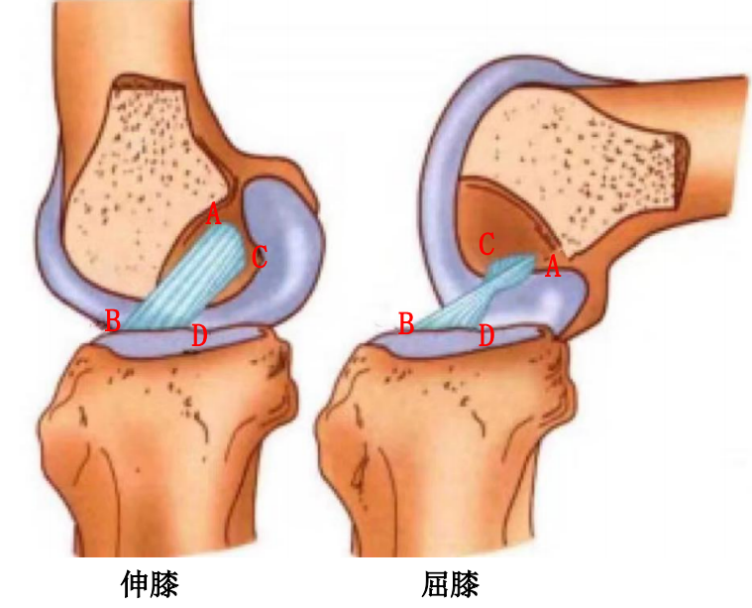

前交叉韧带起自股骨外侧髁的内侧面,斜向前下方,止于胫骨髁间隆起的前部。ACL 分为前内束(AM)和后外束(PL)。当屈膝 30° ~ 40° 时,前交叉韧带的张力最小。

1、限制胫骨前移的主要结构:

在屈膝状态下前内束紧张,主要提供对胫骨前移的抵抗作用。

2、限制过伸:

在伸膝状态下后外束紧张,提供对抗膝关节过伸的主要作用。